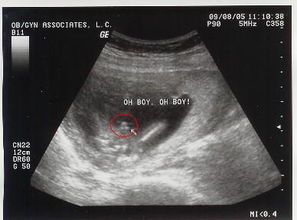

这位准妈妈名叫小雨(化名),是一位体重稍高的孕妇。她在2024年8月的一次产检中,记录下了医生为她做B超的过程。当时,医生一边操作设备,一边开玩笑地说道:“你笑起来真好看,不过肚子里的小家伙好像有点害羞。”这句话让小雨忍俊不禁,她忍不住哈哈大笑起来,而此时的B超画面也因为她的笑声变得格外生动。